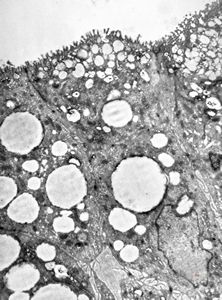

F,8m. | lipid malabsorption - large lipid droplets in enterocytes … semithin section

lipid malabsorption - large lipid droplets in enterocytes … semithin section

lipid malabsorption - large lipid droplets in enterocytes and propria … HE